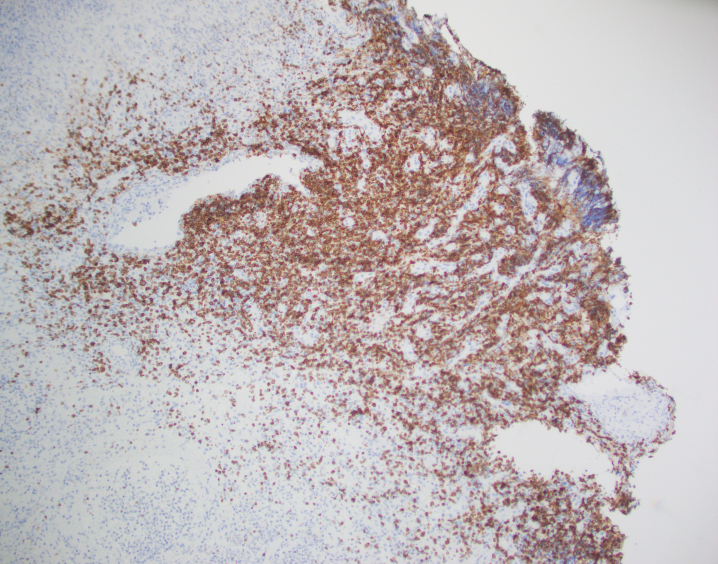

By immunohistochemistry, CD3 highlights the lymphoma cells, which comprise the majority of the lymphoid infiltrate. The lymphoma cells co-express CD56 and CD7 (dim) and are negative for CD2 and CD5. The lymphoma cells also express cytotoxic markers perforin and granzyme (major subset). CD20 highlights only rare small clusters of B-cells. The lymphoma cells are also positive for EBER (Epstein-Barr Virus encoded RNA) in situ hybridization. The Ki67 (MIB1) proliferation index is 60% with focal areas exhibiting up to 80%.